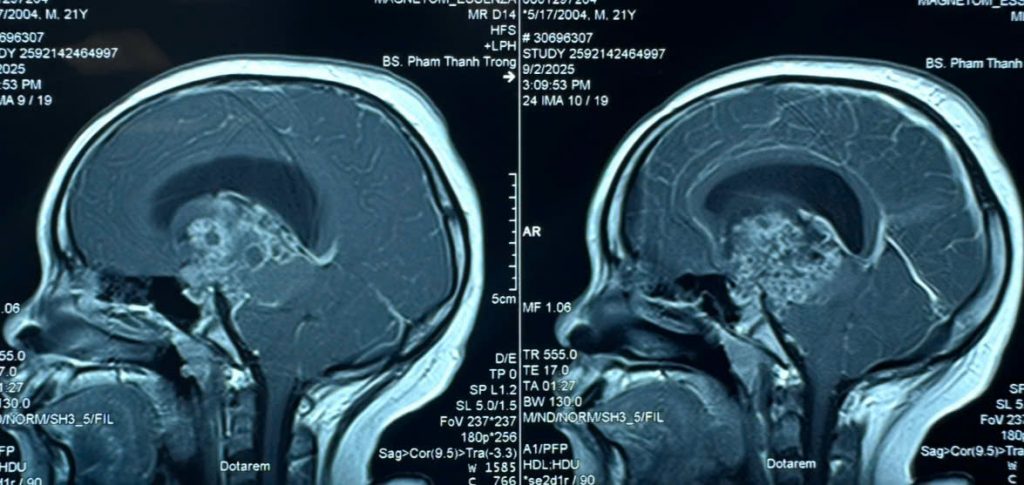

Tiếp nhận người bệnh tại khoa Cấp Cứu, các bác sĩ nhận định người bệnh đã hôn mê sâu, không đáp ứng với môi trường xung quanh – dấu hiệu nghi ngờ não bộ đang bị tổn thương nghiêm trọng. Người bệnh nhanh chóng được tiến hành chụp MRI sọ não. Kết quả cho thấy, anh S. có khối u não lớn kích thước 6cm, khối u nằm ở vị trí giữa não gây chèn ép dẫn đến hiện tượng giãn não thất, làm dịch não tủy không thể lưu thông – nguyên nhân khiến người bệnh rơi vào hôn mê.

Hình ảnh MRI khối u sọ hầu

Theo khai thác bệnh sử, được biết bệnh nhân S. đã từng phẫu thuật lấy khối u sọ hầu cách đây 8 năm. Thời điểm đó, bệnh nhân có chỉ định xạ trị bổ túc sau mổ để điều trị tiếp khối u nhưng vì hoàn cảnh gia đình khó khăn nên bà P. đã ngừng việc điều trị tiếp cho con. Đây có thể là lý do khiến khối u tái phát sớm, khối u ngày càng lớn gây chèn ép não bộ.